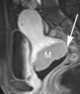

Carcinoma of vagina

Squamous-cell carcinoma of the vagina is a potentially invasive type of cancer that forms in the tissues of the vagina. Though uncommon, squamous-cell cancer of the vagina (SCCV) is the most common type of vaginal cancer. [Source: Wikipedia ]